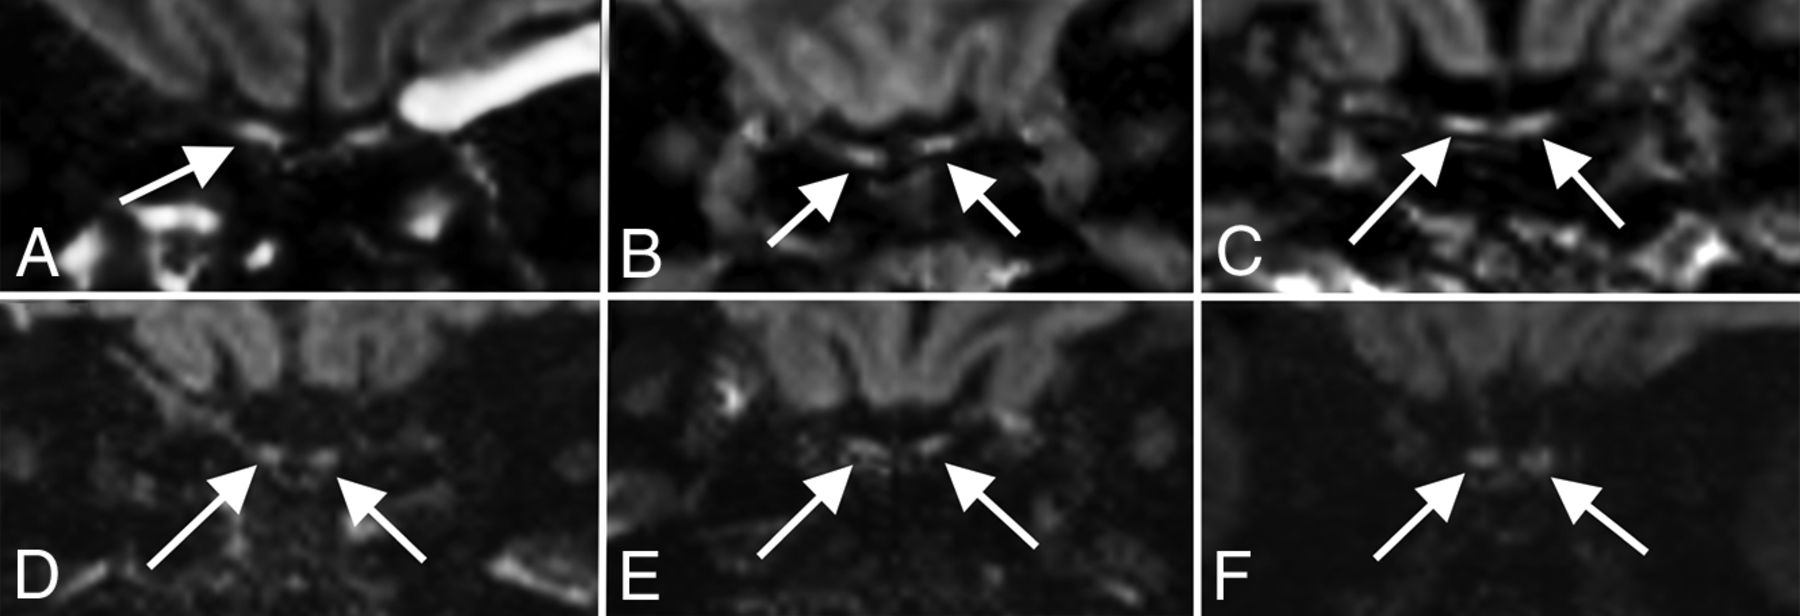

The 3 remaining patients with a greater burden of microhemorrhage had innumerable foci, predominantly involving the splenium of the corpus callosum, along with several foci along the remainder of the corpus callosum, internal capsules, and juxtacortical white matter (Fig 2). There were no foci involving the cortex, deep gray matter, brain stem, or cerebellum. The distribution in these 3 patients was atypical for both cerebral amyloid angiopathy and hypertensive microhemorrhage and, instead, was most compatible with critical illness–associated microhemorrhage.19,20 All 3 patients had prolonged intensive care unit courses with intubation and mechanical ventilation, but none were treated with extracorporeal membrane oxygenation. Two of the 3 had a history of hypertension, and none of the 3 had a history of seizures or antiepileptic medication use. One patient was receiving therapeutic enoxaparin (Lovenox) for deep vein thrombosis, while the other 2 patients were receiving prophylactic Lovenox at the time of imaging. Initial radiology reporting for 2 of these patients raised the possibility of diffuse axonal injury, but none of these patients had a trauma history. Following extubation, all 3 patients had clinical courses complicated by prolonged delirium and altered mental status. Of the patients with fewer than 15 foci of microhemorrhage, 2 additional patients also demonstrated foci only within the splenium of the corpus callosum.

Corpus callosum microhemorrhages. A 65-year-old woman (A), a 44-year-old woman (B), and a 69-year-old man (C) all demonstrate microhemorrhages on SWI, with a similar distribution, preferentially involving the corpus callosum (arrows in A–C), particularly the splenium. All patients had undergone mechanical ventilation before imaging. The distribution is similar to that previously described in critically ill, ventilated patients as well as in those with high-altitude cerebral edema.

Microhemorrhages were found in 26 of 51 patients, with 3 patients demonstrating extensive microhemorrhages predominantly involving the corpus callosum, similar to those shown in a recent case report of a patient with COVID-19 and PRES28 and also in keeping with another recent observational study describing 4 patients with COVID-19 with microhemorrhage in the corpus callosum.29 This pattern of microhemorrhage involving the corpus callosum has also been described in critically ill patients, including those mechanically ventilated for acute respiratory distress syndrome, as well as in patients with high-altitude cerebral edema.19,30 High-altitude cerebral edema microhemorrhages are thought to be due to increased cerebral venous pressure, and positive pressure ventilation may impair cerebral venous return secondary to raised intrathoracic pressure, perhaps explaining the common finding in these 2 distinct patient populations.19 All 3 of our patients with callosal microhemorrhage received mechanical ventilation before MR imaging. Therefore, callosal microhemorrhage in COVID-19 is potentially attributable to mechanical ventilation rather than a direct effect from the virus. These 3 patients did not receive extracorporeal membrane oxygenation, which has previously been reported with callosal microhemorrhages.31 We agree with Radmanesh et al29 that these callosal hemorrhages resemble those seen with diffuse axonal injury, but, as in their study, the clinical history of our patients excludes posttraumatic etiology.